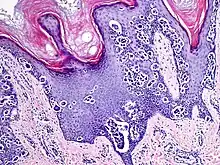

An acral nevus is a cutaneous condition of the palms, soles, fingers, or toes (peripheral body parts), characterized by a skin lesion that is usually macular or only slightly elevated, and may display a uniform brown or dark brown color, often with linear striations.[1]: 1726

They are brown to dark brown in color and have linear streaks of darker pigmentation. Size is usually 7 mm or less, oval or spindle shaped, and well-demarcated. They become stable after an initial growth phase, and the number of lesions also decreases; a new lesion in middle-aged or elderly people should raise suspicion of acral lentiginous melanoma.